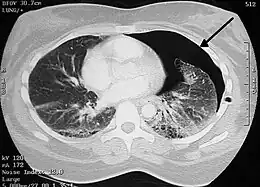

Chest X-ray

A plain chest radiograph, ideally with the X-ray beams being projected from the back (posteroanterior, or "PA"), and during maximal inspiration (holding one's breath), is the most appropriate first investigation.[30] It is not believed that routinely taking images during expiration would confer any benefit.[31] Still, they may be useful in the detection of a pneumothorax when clinical suspicion is high but yet an inspiratory radiograph appears normal.[32] Also, if the PA X-ray does not show a pneumothorax but there is a strong suspicion of one, lateral X-rays (with beams projecting from the side) may be performed, but this is not routine practice.[15][19]

Chest X-ray showing a pneumothorax on the right (left in the image), where the absence of lung markings indicates that there is free air inside the chest

Chest X-ray showing the features of pneumothorax on the left side of the person (right in image)

It is not unusual for the mediastinum (the structure between the lungs that contains the heart, great blood vessels, and large airways) to be shifted away from the affected lung due to the pressure differences. This is not equivalent to a tension pneumothorax, which is determined mainly by the constellation of symptoms, hypoxia, and shock.[13]

The size of the pneumothorax (i.e. the volume of air in the pleural space) can be determined with a reasonable degree of accuracy by measuring the distance between the chest wall and the lung. This is relevant to treatment, as smaller pneumothoraces may be managed differently. An air rim of 2 cm means that the pneumothorax occupies about 50% of the hemithorax.[15] British professional guidelines have traditionally stated that the measurement should be performed at the level of the hilum (where blood vessels and airways enter the lung) with 2 cm as the cutoff,[15] while American guidelines state that the measurement should be done at the apex (top) of the lung with 3 cm differentiating between a "small" and a "large" pneumothorax.[33] The latter method may overestimate the size of a pneumothorax if it is located mainly at the apex, which is a common occurrence.[15] The various methods correlate poorly but are the best easily available ways of estimating pneumothorax size.[15][19] CT scanning (see below) can provide a more accurate determination of the size of the pneumothorax, but its routine use in this setting is not recommended.[33]

Not all pneumothoraces are uniform; some only form a pocket of air in a particular place in the chest.[15] Small amounts of fluid may be noted on the chest X-ray (hydropneumothorax); this may be blood (hemopneumothorax).[13] In some cases, the only significant abnormality may be the "deep sulcus sign", in which the normally small space between the chest wall and the diaphragm appears enlarged due to the abnormal presence of fluid.[16]